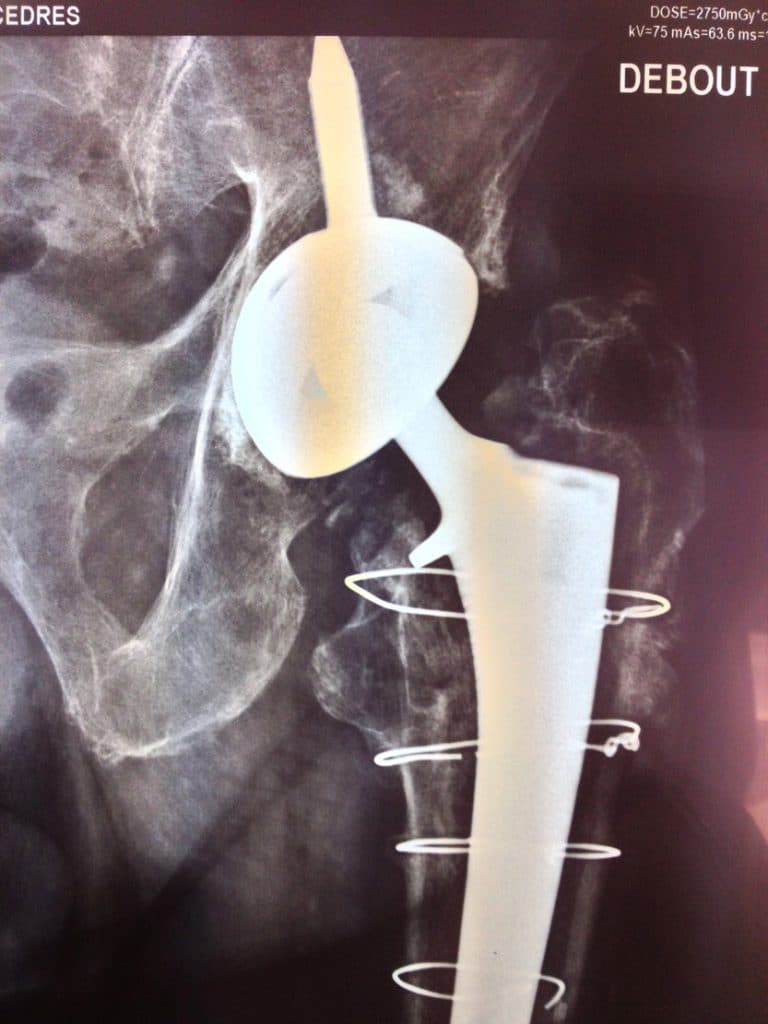

Le scanner confirmait le présence d’une poutre ilio ischiatique compatible avec l’utilisation du cotyle INTEGRA™.

Effet “jumbo cup ” (56) , ascension et appui sur la corticale du toit du néocotyle.

Pivot fémoral Press Fit sans ciment.

Notez que le plot d’ancrage iliaque du cotyle cimenté est exactement situé au point d’introduction du plot iliaque du cotyle INTEGRA™.